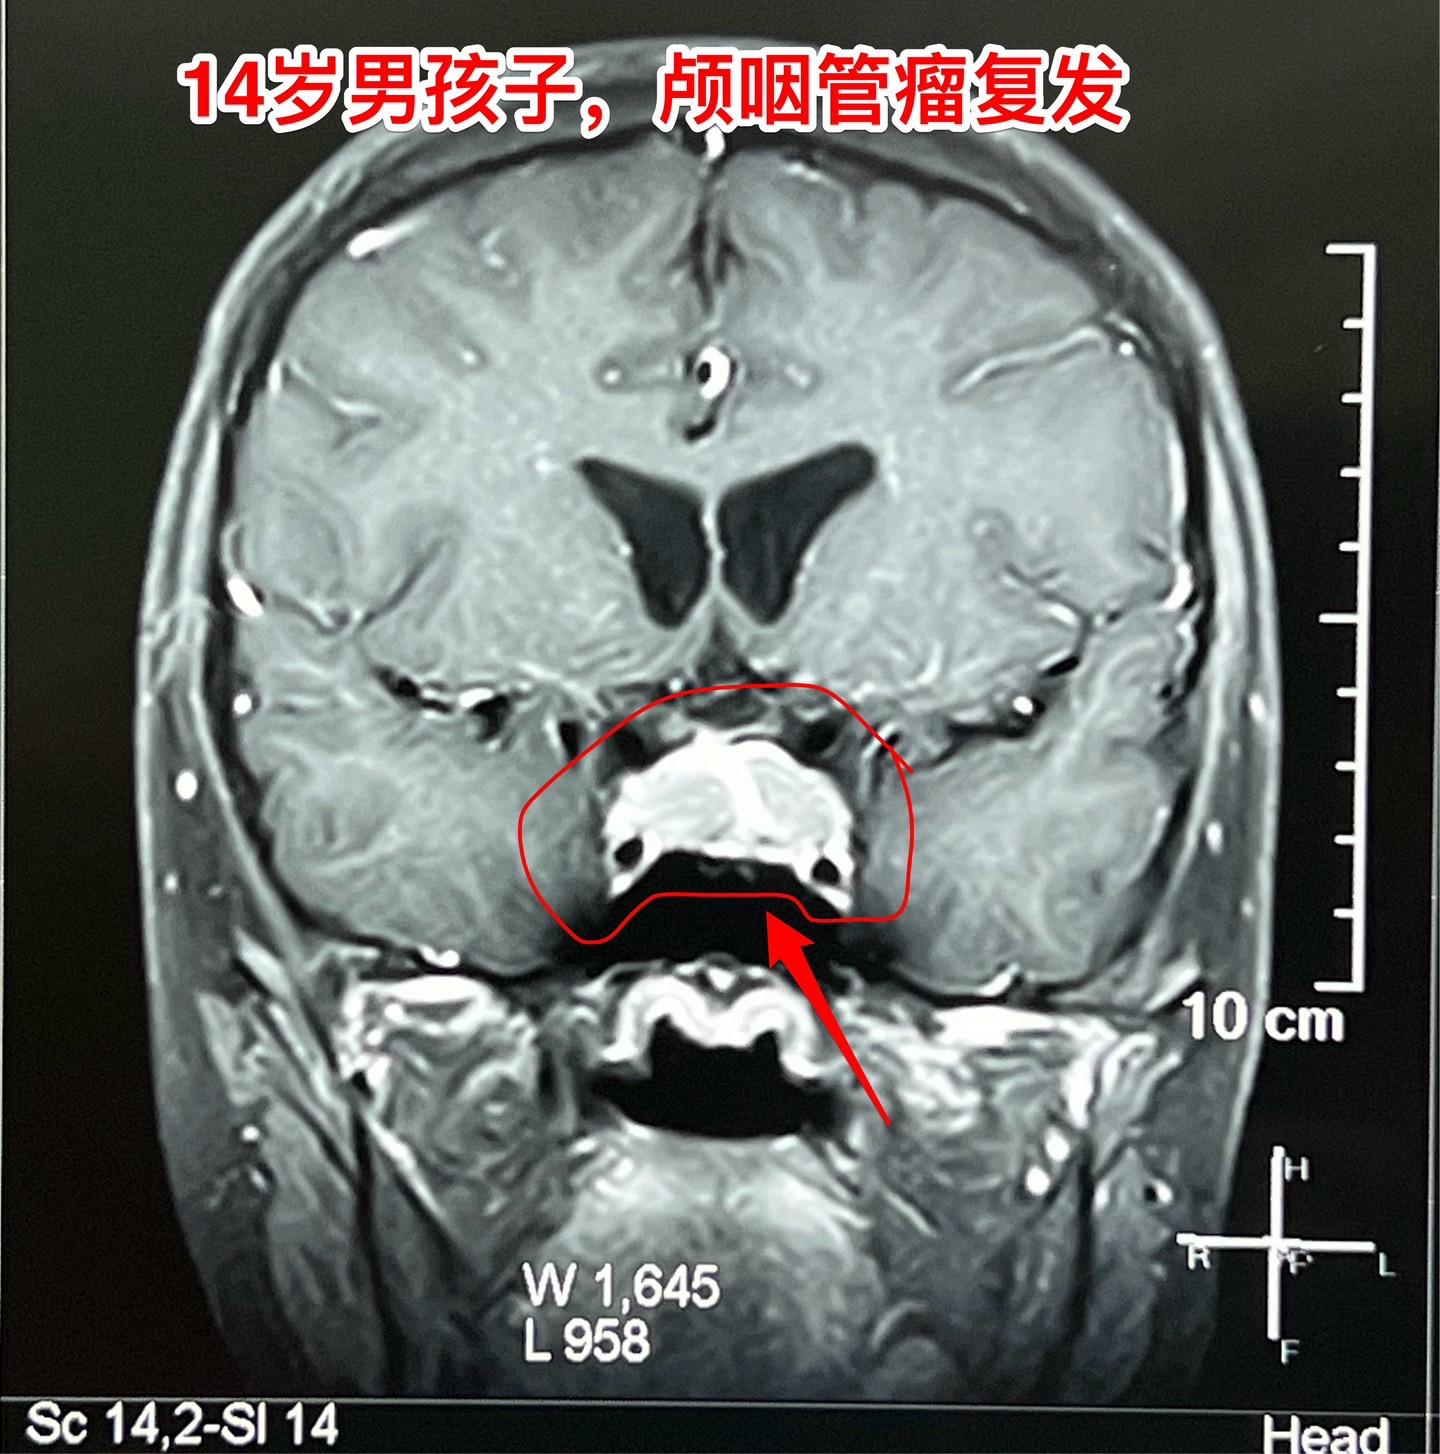

12月26日两个颅咽管瘤手术。第一个四岁男孩子,因为头部受伤,作CT发现颅咽管瘤。家长没有犹豫,选择尽快作手术。手术中将颅咽管瘤完全切除,垂体柄和垂体保留约50%。早作手术的好处就是肿瘤与周围结构粘连不紧密,易于分离,有助于完全切除肿瘤。 第二个病人是14岁男孩子,颅咽管瘤手术后6年,术后半年就发现了肿瘤复发,随后观察,多次复查磁共振显示肿瘤在长大。这个瘤也是在垂体窝内,和第一个病人一样,但是肿瘤与周围结构粘连紧密,切除的难度更大,也得到了完全切除。